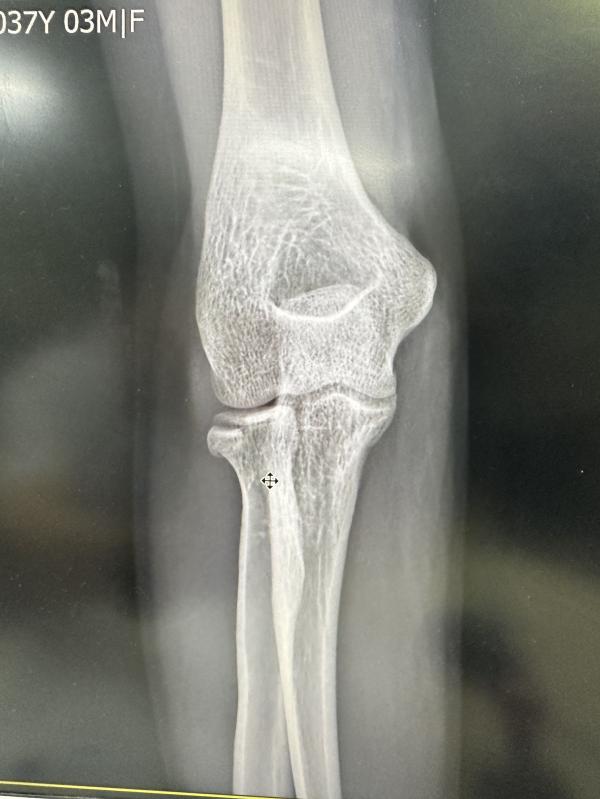

Моя детская мечта кататься на сёрф-скейте обернулась для меня сломанной правой рукой.

Гипс наложили в больнице и сказали что нужно делать операцию.

Есть ли среди вас хирурги, кто может посмотреть на снимок, который я приложила, как на ваш взгляд, действительно ли нужно делать операцию?

Потому что я заметила что операции они делаю здесь практически при каждом переломе.